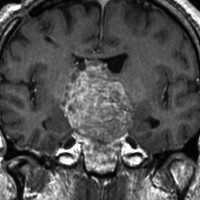

典型的なMRIの画像です

下垂体腺腫のMRIです。両側の視野障害(両耳側半盲)のために手術を受けた患者さんのものです。この腫瘍は非機能性腺腫といってホルモンを出さない腫瘍でした。少し大きめでしたが全部取れて視野の障害はよくなりました。

左の2枚はガドリニウム造影剤を使って写したもので腫瘍の形がよくわかります。右の1枚はT2強調画像と言います。MRIでは撮影の仕方によって見え方が違います。